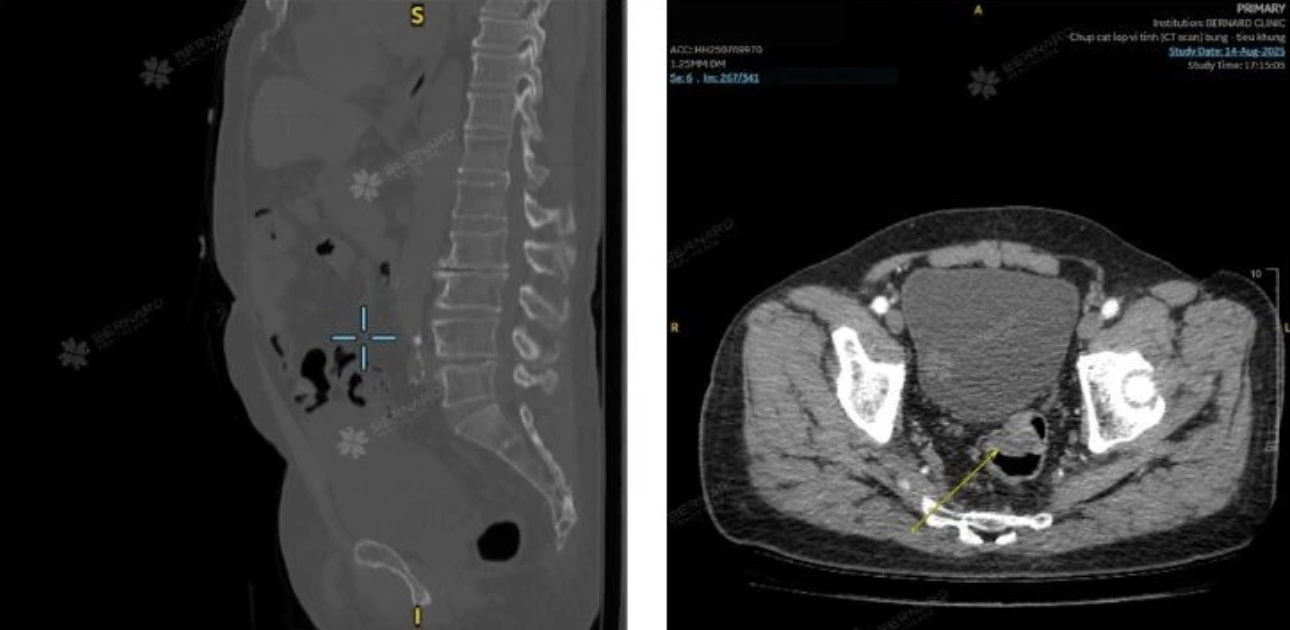

Qua khai thác tiền sử và thăm khám ban đầu, bác sĩ tại Phòng khám Bernard chỉ định các xét nghiệm cần thiết, trong đó có CT scan bụng - chậu có tiêm thuốc cản quang nhằm sàng lọc tổn thương tiềm ẩn.

Kết quả CT scan ghi nhận khối choán chỗ ở trực tràng giữa, kích thước khoảng 2,5 x 3,0 cm, đậm độ trung bình, bắt quang không đồng nhất. Để làm rõ bản chất tổn thương và tránh bỏ sót, bác sĩ tiếp tục chỉ định nội soi toàn bộ đại trực tràng.